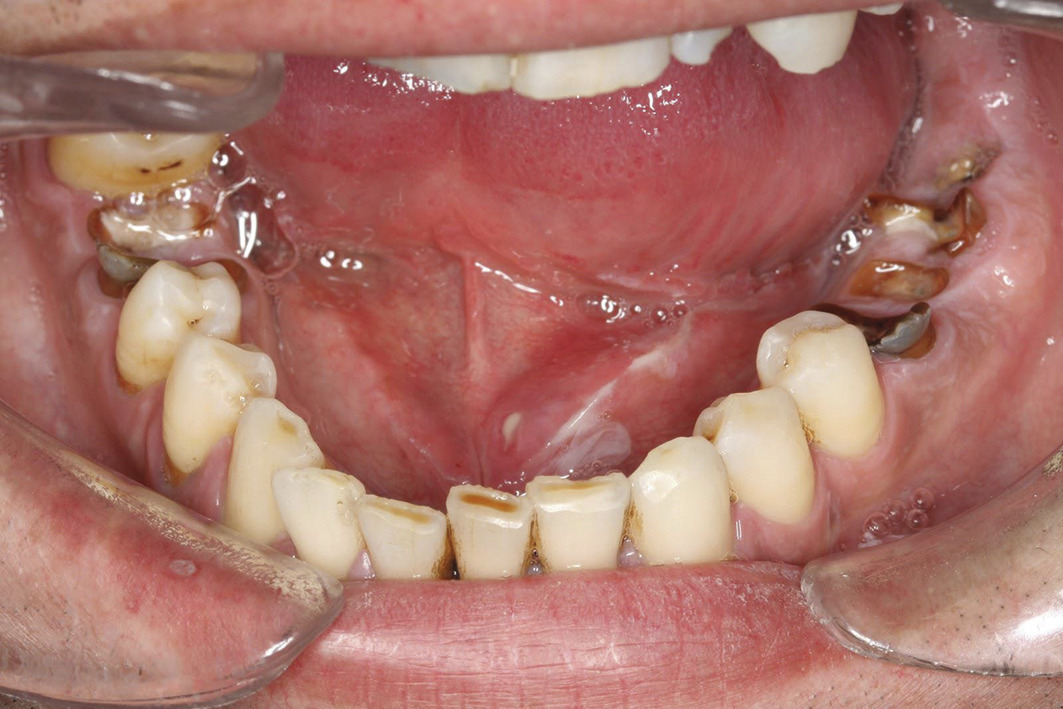

Sur le plan clinique, le syndrome sec se traduit par :

• la xérostomie, qui est le motif le plus fréquent de consultation. Les signes cliniques sont une muqueuse sèche et collante, une absence de lac salivaire au plancher buccal et une absence d’écoulement salivaire aux ostia à la palpation glandulaire. Une chéilite, une atrophie papillaire ou encore des caries aux collets des dents sont des signes indirects ;